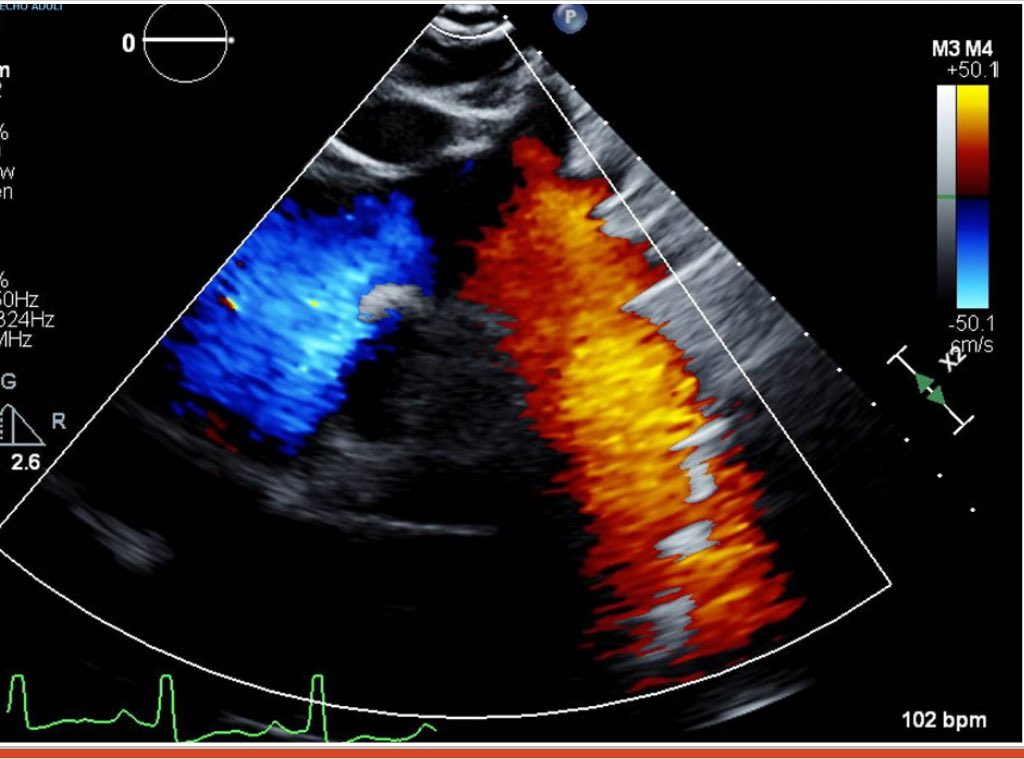

☢️What is the biggest aorta you have seen? 🤯 📢 How would you grade the severity of the AR? Dr. Purvi Parwani Ritu Thamman MD #ACCImaging American College of Cardiology Juan Lopez-Mattei, MD Juan Batlle, MD, MBA Manish Motwani Maros Ferencik Thanks for sharing Carlos Gongora, MD FACC